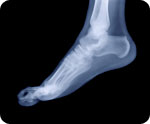

Osteoporosis

(NaturalNews) The naturally occurring polyphenols in dried plums (prunes) may encourage bone formation and reduce the risk of osteoporosis, according to a study conducted by researchers from Oklahoma State University and the University of Oklahoma Health Sciences, and published in the Journal of Nutritional Biochemistry.

And estimated 75 million people in the United States, Europe and Japan suffer from osteoporosis. Many of these are treated using drugs with the potential for long-term side effects.